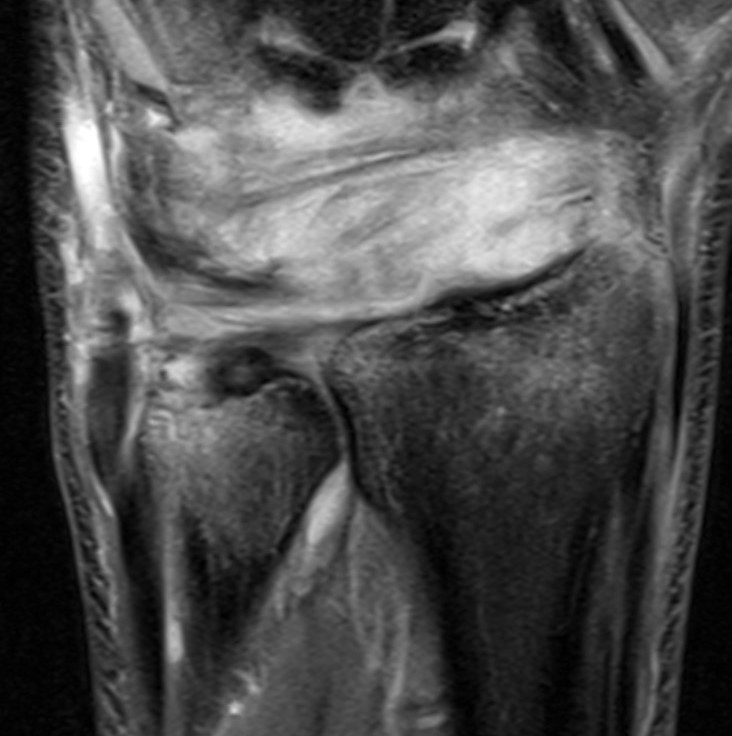

MRI

MRI demonstrating dorsal distal ulna subluxation associated with significant ligament disruption